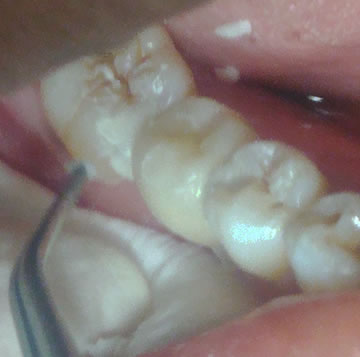

Clinical case

For more than 15 years, the patient feared an invasive and expensive restoration for a missing tooth 36. A 3D GATEWAY™ anchoring is performed on each support tooth 35 and 37, where a decay is neat, without excessive trimming. A dental impression is made, then sent to laboratoire Delprat.